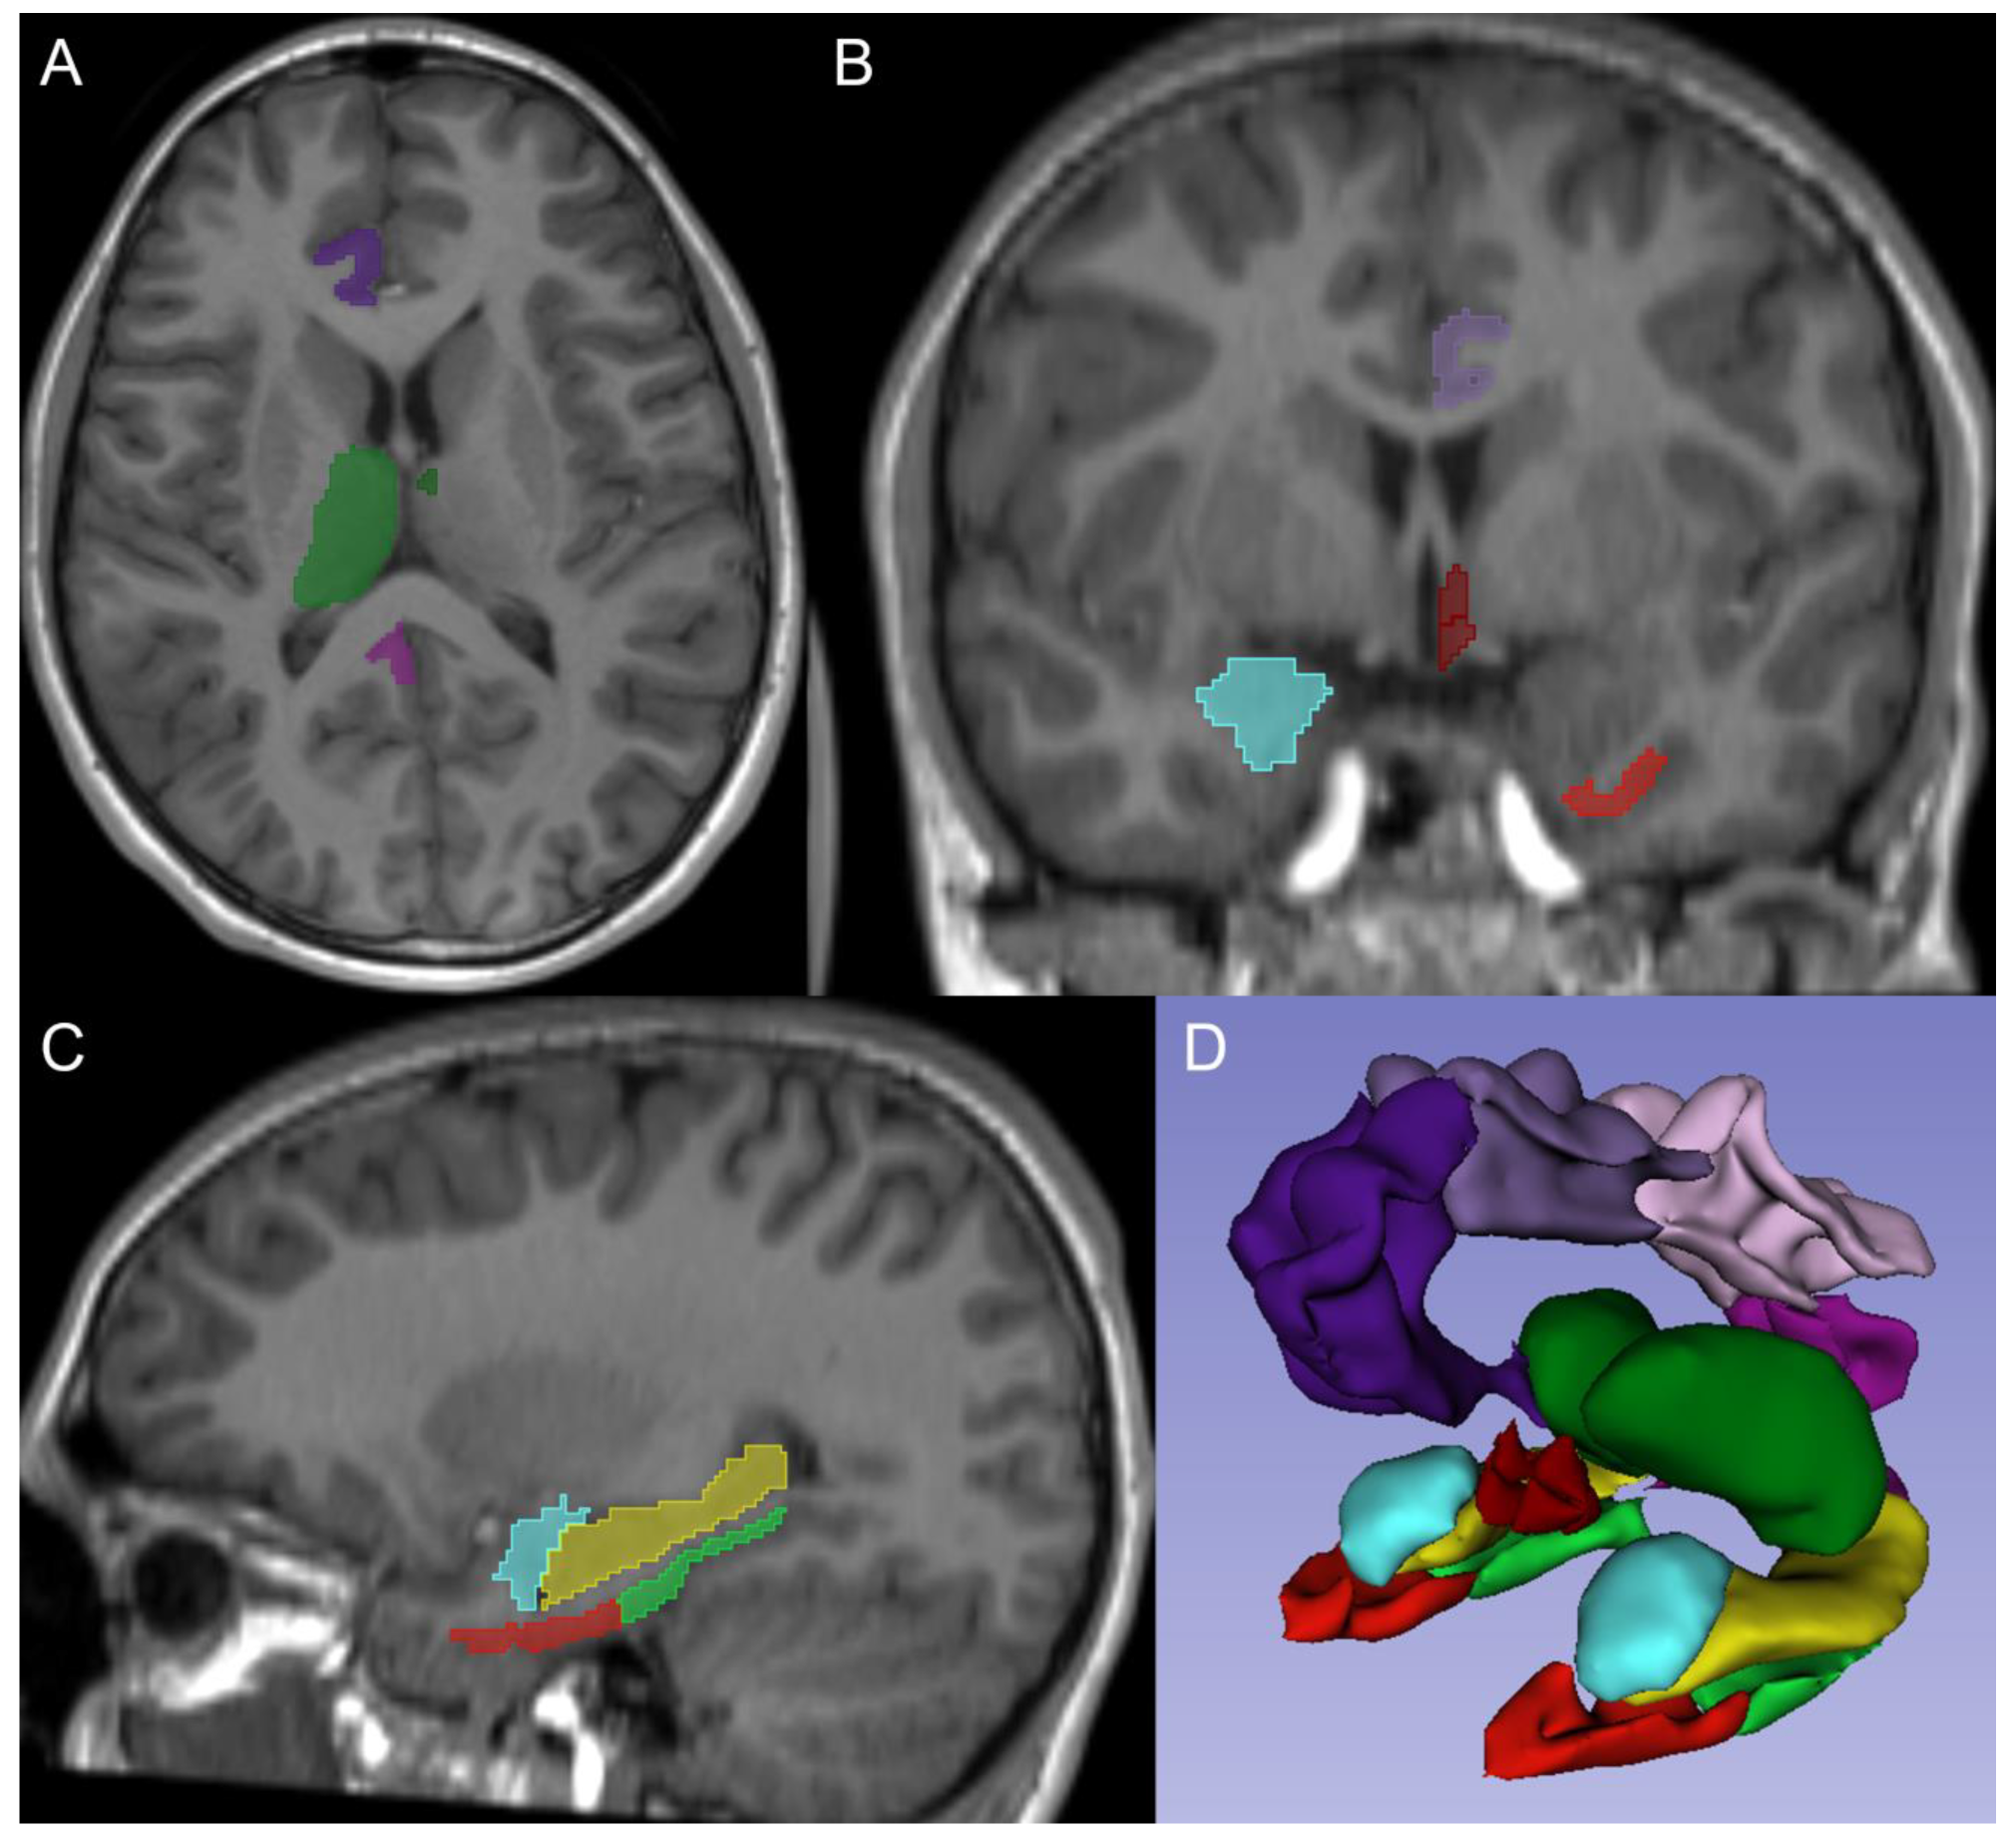

MRI Volumetric Analysis of the Hypothalamus and Limbic System across the Pediatric Age Span